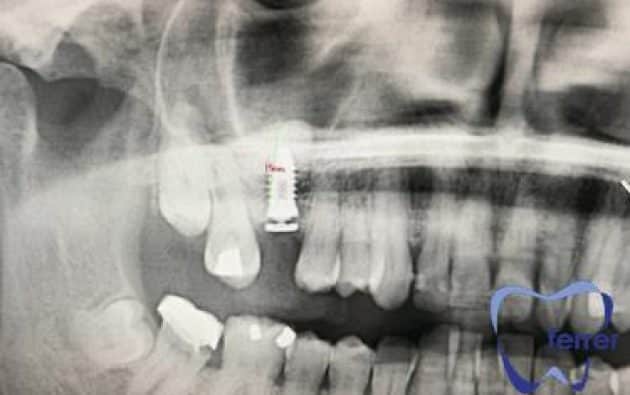

Durante esta valoración inicial, realizamos un escáner 3D o TAC dental de alta precisión que nos permite observar en detalle la cantidad y calidad del hueso disponible.

Esta imagen tridimensional nos ayuda a planificar el injerto con total seguridad, definiendo el volumen necesario y localizando estructuras anatómicas importantes como el nervio dentario o el seno maxilar.

Mediante revisiones clínicas y nuevas pruebas de imagen, confirmamos que la regeneración ósea avanza correctamente antes de programar la colocación del implante. Así garantizamos un resultado predecible, seguro y duradero.